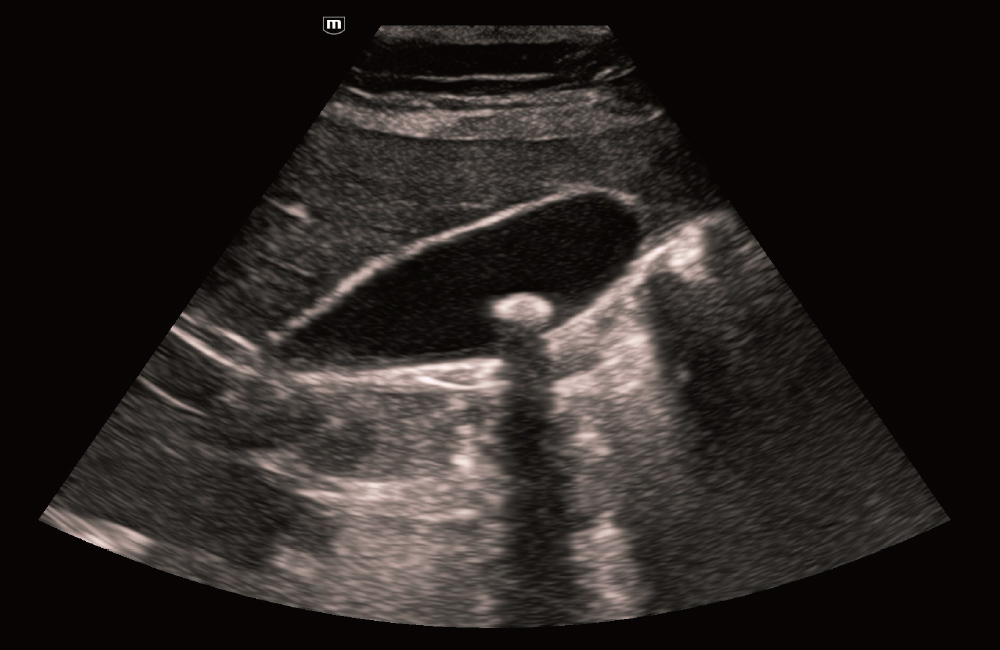

VesĂcula biliar com o iTouch+